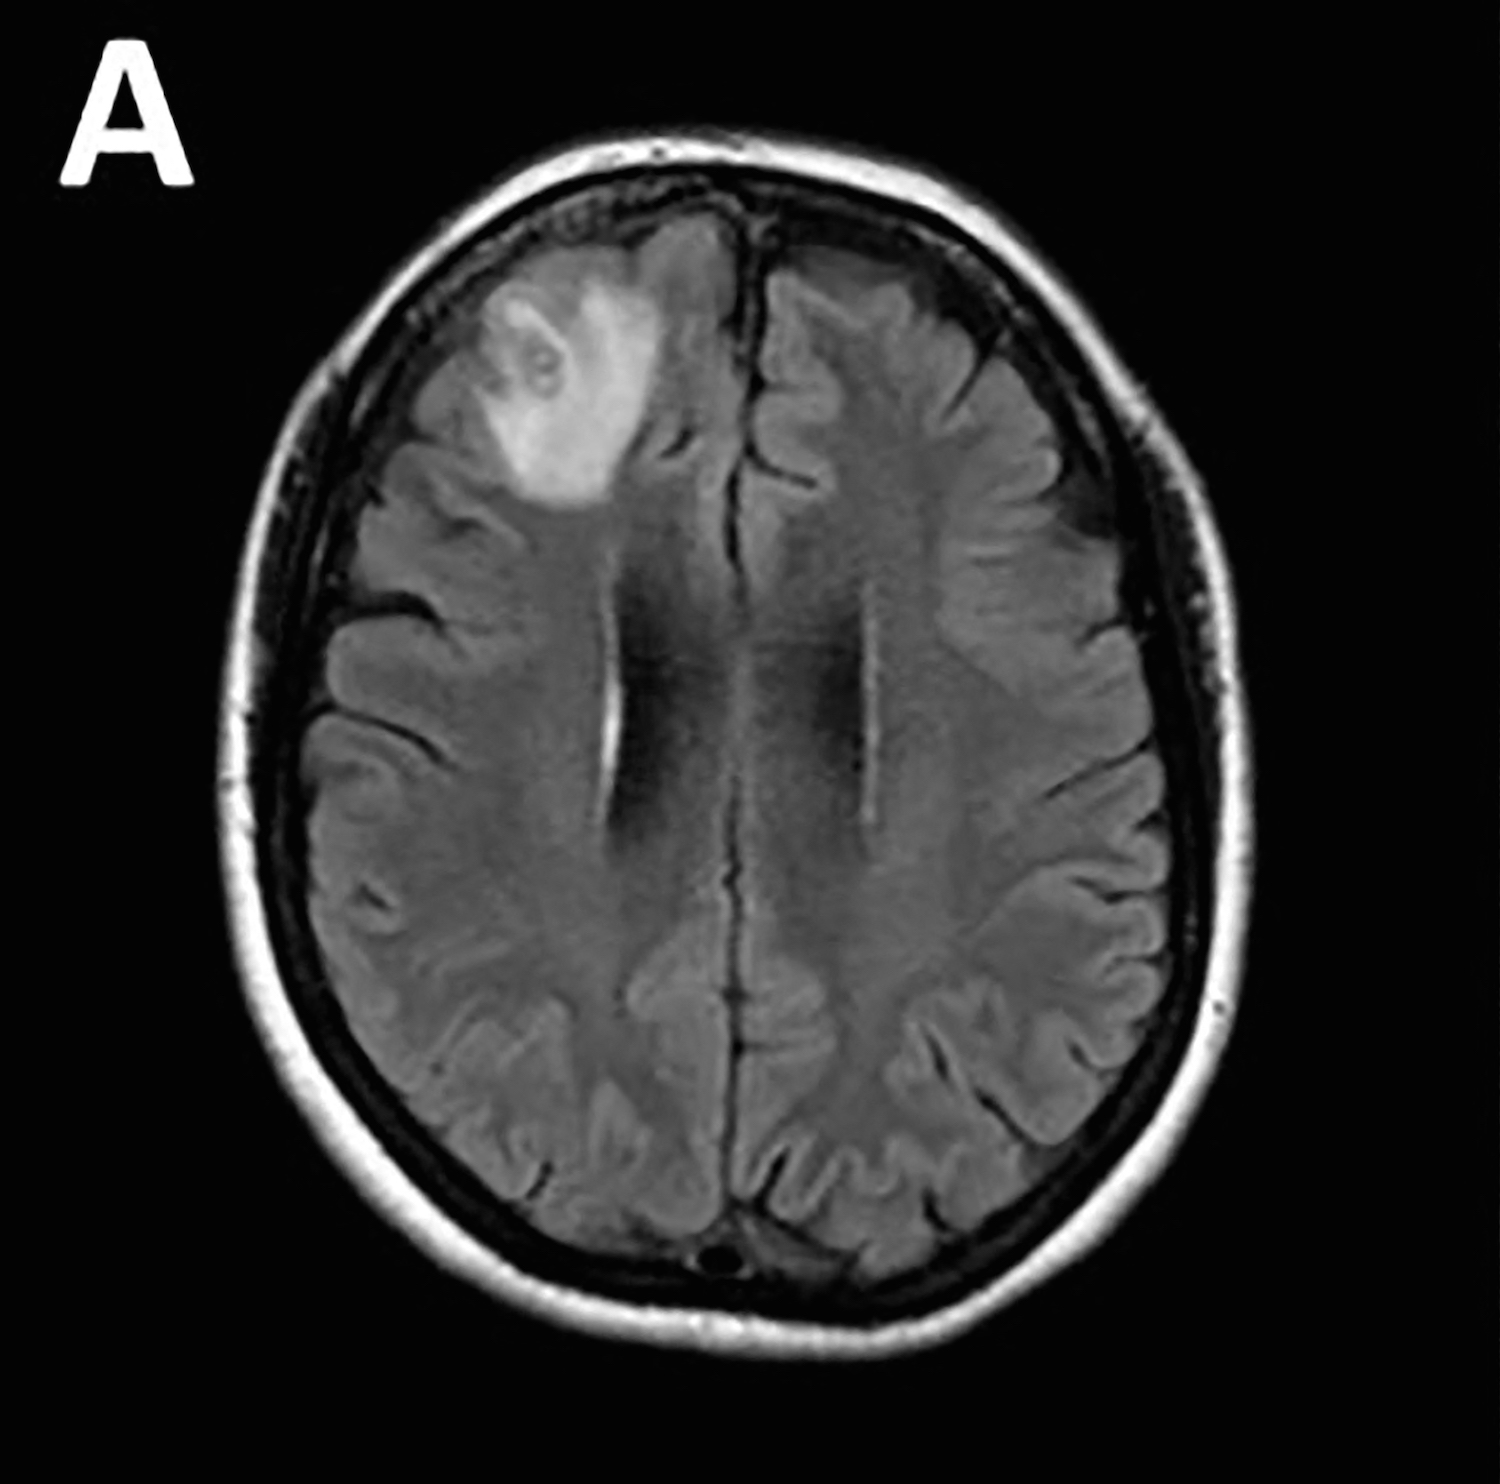

TOPSHOT – An undated and unplaced handout phooto received from The Australian National University (ANU) in Canberra on August 29, 2023 shows a brain scan. A parasitic roundworm typically found in snakes has been pulled “alive and wriggling” from a woman’s brain in a stomach-churning medical first, Australian doctors said on August 29, 2023. (Photo by Handout / THE AUSTRALIAN NATIONAL UNIVERSITY / AFP)

Baffled doctors performed an MRI scan on the 64-year-old Australian woman after she began suffering memory lapses, noticing an “atypical lesion” at the front of her brain.

She was re-admitted to a hospital three weeks later when her condition did not improve, and underwent various treatments until brain scans revealed a lesion and an open biopsy was performed in June 2022.